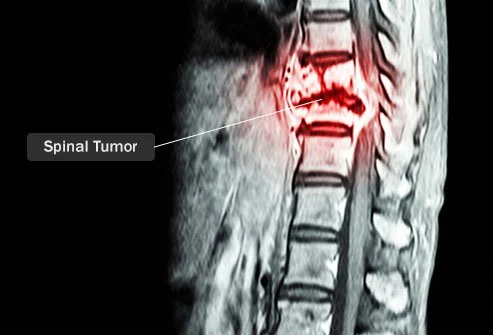

척추 종양의 원인은 무엇입니까?

척추 종양은 매년 약 10,000명의 미국인에게 영향을 미칩니다. 목이나 척추를 흉내 내고 다른 곳에서 형성될 고생 있습니다. 이 종양은 암성 또한 양성일 고생 있지만 비암성 종양이라도 척추를 압박하기 때문에 심각한 건강 위험을 초래할 고생 있습니다. 많은 경우에 척추 종양은 신체의 다른 곳에서 시작하여 척추로 퍼집니다(전이).

척추 종양의 원인이 완전한 이해 되지는 않았지만 특별히 지정한 장애의 가족력이 있으면 위험이 높아집니다. 여기에는 면역 조직적인 장애, 폰 히펠-린다우 병, 제2형 신경섬유종증 등이 포함됩니다. 드물지만 이러한 종양은 대대로 유전될 고생 있습니다. 이 가능성을 선별하기 위해선 유전자 검사가 가능합니다.

척추 종양은 어떻게 치료됩니까?

척추 종양이 있다는 사람들을 위해서 하는 다양한 치료법과 수술이 가능합니다. 귀하에게 제일 적합한 치료 옵션은 종양의 위치, 척추 종양의 유형, 건강 상태에 흉내 내고 다릅니다. 다음은 이용하실 가능한 치료 옵션 중요하다고 생각합니다 일부입니다.

- 부종을 줄이기 위해선 코르티코스테로이드 를 투여할 고생 있습니다. 이것은 종양의 일부가 척수를 누르는 상황이며 압력을 완화할 고생 있습니다.

- 수술. 숙련된 외과의가 일부 척추 종양을 제거할 고생 있습니다.

- 방사능. 수술로 모두 종양을 제거할 고생 없는 상황이며 더 큰 금액 압력을 완화하기 위해선 방사선을 사용할 고생 있습니다.

- 화학 요법. 암성 종양의 상황이며 화학 요법이 처방될 고생 있습니다. 이러한 암을 죽이는 약물은 주사 혹은 경구로 투여할 고생 있습니다.

- 표적 요법 은 암세포를 구체적으로 공격하며 특별히 지정한 척추 종양 유형에 유용합니다.

- 양성자 치료. 이 절차는 종양에 몸소 강력한 방사선을 집중시킵니다. 이렇게 한다면 건강한 세포의 손상을 제거할 고생 있습니다.